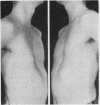

Pectus excavatum is a progressive congenital deformity for which surgical correction is an established procedure. The method of correction using a stainless steel retrosternal bar to maintain the sternum elevated is, in our experience, the most successful procedure. Successful surgical correction usually requires resection of all deformed costal cartilages with transverse osteotomy of the anterior table of the sternum and internal fixation using a bar anterior to the rib cage but behind the sternum. In the last 13 years 118 patients with this deformity have been evaluated and 72 patients have been surgically corrected by the described procedure. Of these 72 patients, 65 (90 percent) have had excellent or good cosmetic and functional results. The best results were obtained when the child was operated on between the ages of 6 and 10 years, the poorest results in those operated on under the age of 3 or over the age of 20. For a satisfactory result the bar must be left in for at least six months; the best results were obtained in those patients in whom the bar was left in for at least one year. No serious complications have followed the use of this technique.